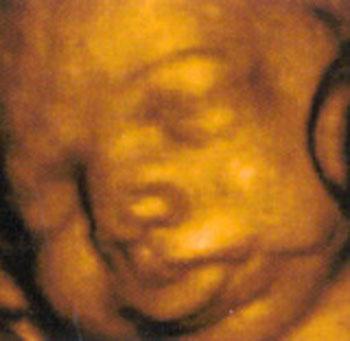

Ультразвуковые съёмки аборта на 12 неделе явно показывают: ребёнок чувствует боль, как любой из нас, и прекрасно понимает, что его хотят убить - он всеми силами старается отодвинуть от себя инструмент и широко раскрывает рот в безмолвном крике, когда у него отрывают сначала ноги, затем часть туловища…

Голову извлекают в последнюю очередь и лицо убитого ребёнка всегда искажено гримасой боли и ужаса. По этим кадрам видно, что практически нет разницы, убить ли 3-месячного ребёнка в утробе или отрезать руки -ноги -голову 5-летнему малышу. Без анестезии и в полном сознании.

- Фильм американского врача Бернарда Нэйтансона, названный «Безмолвный крик», показал всему миру, что такое аборт на сроке 11 недель беременности. Многие врачи и медсестры, посмотрев фильм, прекратили участвовать в абортах.

Это документальный фильм, и авторы рекомендуют соблюдать осторожность при его показе, поскольку некоторые кадры могут вызвать у человека психологический шок: безмолвный крик внутриутробного младенца, искаженное от боли лицо ребенка, погибающего на наших глазах...

Из закадрового текста к фильму: «Инструмент еще не коснулся ребенка, но он уже возбужден, его сердечные удары учащаются и достигают приблизительно 200 ударов в минуту. Вакуум-кюретка нащупывает ребенка, и он широко раскрывает рот в безмолвном крике».